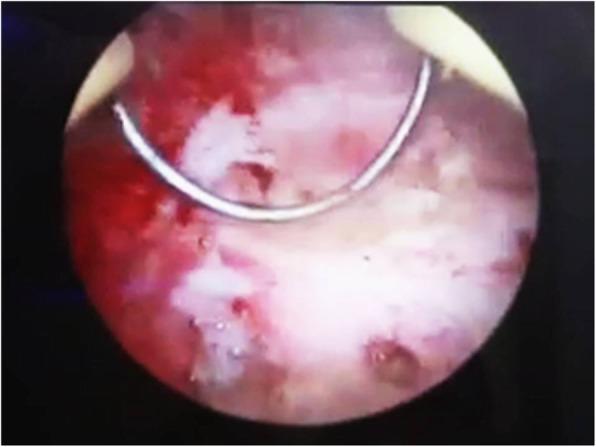

In this study, a case of copper IUD migration through cesarean scar defect is presented, in such a way that was successfully managed by cystoscopic removal. A 31-year-old female with a history of lower urinary symptoms referred to the clinic for her secondary infertility work-up. A copper IUD outside the uterus in the bladder was found using hysterosalpingraphy. A plain abdominal radiography also confirmed the presence of a T-shaped IUD in the pelvis. According to ultrasound, the copper IUD was partly in the bladder lumen and within the bladder wall. The patient had a history of an intrauterine device insertion eight years ago followingher second cesarean delivery. Three years later, her IUD was expelled, and another copper IUD was inserted. Thesecond copper IUD was alsoremoved while she decided to be pregnant. The patient finally underwent a hysteroscopic cystoscopy. The intrauterine device with its short arms embedded in the bladder wall was successfully extracted through the urethra.